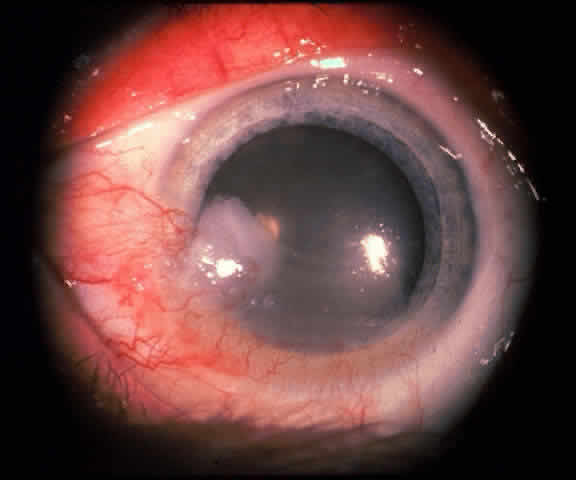

The epithelial dysplastic lesions—conjunctival intraepithelial neoplasia and squamous cell carcinoma—almost always begin at the limbus, most commonly in the interpalpebral zone.57,58 The initial appearance is a gelatinous, gray lesion with some thickening (Fig. 3). There may be increased vascularization. The epithelial changes may extend onto the cornea, causing a hazy, gray appearance. Tumor vascularity lags behind the lead margin of the epithelial change. As the lesions progress from dysplastic to carcinomatous, they become thicker, more vascularized and may show keratinization, giving a leukoplakic appearance (Fig. 4). Lesions confined to the epithelium move freely over the sclera, whereas invasive lesions are fixed to underlying tissue. Occasionally squamous cell carcinomas appear identical to classic papillomas.

Fig. 8. Conjunctival intraepithelial neoplasia. Gray, gelatinous mass is centered at limbus and has prominent vessels. A veil of intraepithelial disease extends laterally across the inferior third of the cornea.

Early dysplastic lesions (conjunctival intraepithelial neoplasia) show thickened epithelium with extension of basal-like cells beyond the basal layer, but cells continue to mature into flat squamous cells. Mitoses are also seen higher in the epithelium. As the degree of dysplasia worsens, the more superficial epithelium is replaced at higher levels by basal-type cells, mitoses can be seen further from the basal layer, and atypia of cells becomes more pronounced. With squamous cell carcinoma in situ, there is full-thickness dysplasia, cellular atypia is variable, and mitoses can be seen at all layers of the epithelium. Invasive squamous cell carcinomas are usually well differentiated. Pleomorphism, hyperchromaticity, dyskeratosis, and horn pearls are seen. Epithelial cell clusters can be seen invading below the basement membrane. Inflammatory cells are common in the substantia propria.